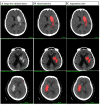

This study aims to develop and validate an artificial intelligence model based on deep learning to predict early hematoma enlargement (HE) in patients with intracerebral hemorrhage. A total of 1,899 noncontrast computed tomography (NCCT) images of cerebral hemorrhage patients were retrospectively analyzed to establish a predicting model and 1,117 to validate the model. And a total of 118 patients with intracerebral hemorrhage were selected based on inclusion and exclusion criteria so as to validate the value of the model for clinical prediction. The baseline noncontrast computed tomography images within 6 h of intracerebral hemorrhage onset and the second noncontrast computed tomography performed at 24 ± 3 h from the onset were used to evaluate the prediction of intracerebral hemorrhage growth. In validation dataset 1, the AUC was 0.778 (95% CI, 0.768-0.786), the sensitivity was 0.818 (95% CI, 0.790-0.843), and the specificity was 0.601 (95% CI, 0.565-0.632). In validation dataset 2, the AUC was 0.780 (95% CI, 0.761-0.798), the sensitivity was 0.732 (95% CI, 0.682-0.788), and the specificity was 0.709 (95% CI, 0.658-0.759). The sensitivity of intracerebral hemorrhage hematoma expansion as predicted by an artificial intelligence imaging system was 89.3%, with a specificity of 77.8%, a positive predictive value of 55.6%, a negative predictive value of 95.9%, and a Yoden index of 0.671, which were much higher than those based on the manually labeled noncontrast computed tomography signs. Compared with the existing prediction methods through computed tomographic angiography (CTA) image features and noncontrast computed tomography image features analysis, the artificial intelligence model has higher specificity and sensitivity in the prediction of early hematoma enlargement in patients with intracerebral hemorrhage.